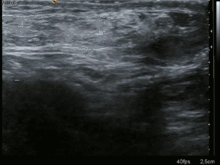

After the diagnosis is suspected, it is often confirmed by imaging. When assessed by ultrasound or cross sectional imaging with CT or MRI, the major differential in diagnosing indirect inguinal hernias is differentiation from spermatic cord lipomas, as both can contain only fat and extend along the inguinal canal into the scrotum.[9]

On axial CT, lipomas originate posterolateral to the cord, and are located inside the cremaster muscle, while inguinal hernias lie anteromedial to the cord and are not intramuscular. Large lipomas may appear nearly indistinguishable as the fat engulfs anatomic boundaries, but they do not change position with coughing or straining.[9]